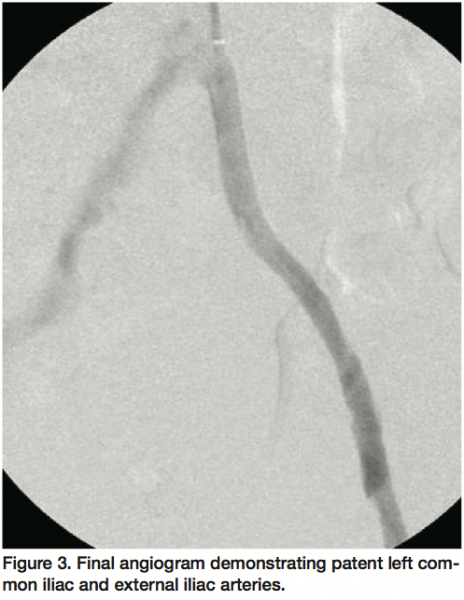

The procedure was performed in the surgical suite with a portable C-arm fluoroscopic imaging unit with the patient under regional anesthesia. A 7 Fr 90 cm Shuttle sheath (Cook Medical) was used to cannulate the left CIA via high right brachial artery access and the lesion crossed using a Frontrunner® XP CTO catheter (Cordis). Meanwhile, an open surgical common femoral endarterectomy (duplex ultrasound prior to the procedure confirmed a short segment of patent but diseased CFA with retrograde flow from the collaterals) and profunda femoris profundoplasty was performed to allow inflow into the left foot via the profunda femoris and collaterals to the popliteal artery. A Micro Guide Catheter XP (Cordis) was advanced over the Frontrunner catheter; a 260 cm 0.035 inch straight tip stiff Aquatrack® wire (Cordis) was directed through the Micro Guide catheter; the wire exteriorized through the common femoral endarterectomy site; and the femoral artery clamped over the wire at the inguinal ligament (Figure 2). Balloon angioplasty was performed in the left CIA and left external iliac arteries (EIA) using a 6 x 100 mm Powerflex balloon (Cordis) with multiple inflations at a maximum pressure of 8 atmospheres. A 10 x 38 mm iCAST™ covered stent (Atrium Medical) was deployed in the left CIA with one inflation at 10 atmospheres followed by post-dilatation using a 9 x 40 mm Powerflex balloon (Cordis) with 2 inflations at a maximum pressure of 12 atmospheres. An adjacent self-expanding SMART® nitinol stent (Cordis) was placed overlapping the CIA stent and extending to the inguinal ligament followed by post-dilatation using a 9 x 40 mm Powerflex balloon (Cordis) with 5 inflations at a maximum pressure of 10 atmospheres. The distal end of the exteriorized wire was directed into the profunda femoris artery and the femoral artery unclamped, the endarterectomy perfected, and the surgical site irrigated and closed in layers. Subsequent angiography confirmed patent left CIA and EIA (Figure 3) and good single vessel runoff into the foot. The patient was monitored for 36 hours and discharged home on postoperative day 2 with minimal restrictions and wound care instructions. Patient was seen at 1 month follow-up with significant improvement in symptoms and patent common femoral and profunda femoris arteries by arterial duplex ultrasonography with an improved ankle-brachial index of 0.79.